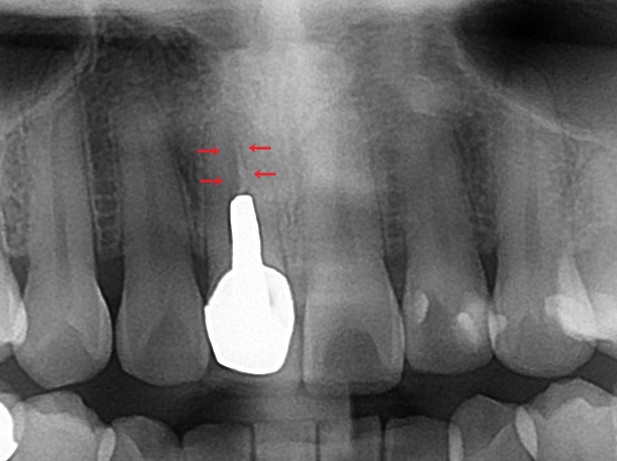

矢印の箇所ですが、神経のあった根管が黒く写っています。

本来は根管治療がしっかりされていると、材料が入るために白くレントゲン写真で写ります。

根管治療を行ない、消毒した根管を薬剤で密閉しています。材料がレントゲン写真で白く写るので、根管治療がしてあるのが分かります。

神経を治療した歯は茶色く、黒く変色してくるのですが、特にしっかりと根管治療がされていない歯は濃く変色します。